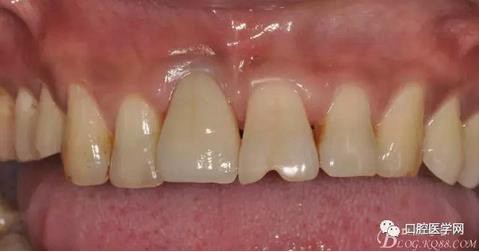

影響進食和美觀,來我院就診

圖4 術(shù)前正位頜面照